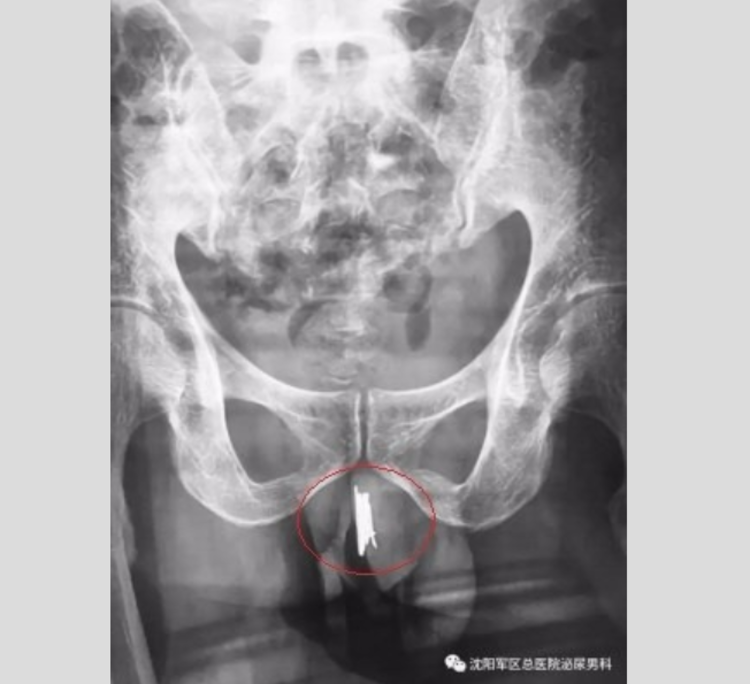

Um homem de 35 anos foi parar no hospital de Shenyang (China) após introduzir 15 agulhas de costura no pênis para sentir prazer. Ele passou por uma cirugia emergencial para remover os itens, a história viralizou na internet.

O paciente, não identificado, deu entrada na unidade de saúde com aguas de 10 centímetros na uretra. Segundo o Daily Mail, ele sentia fortes dores e tinha sangramento ao urinar.

Para remover as agulhas, o cirurgião usou um fia metálico para atrair os objetos. O procedimento levou uma hora e meia.